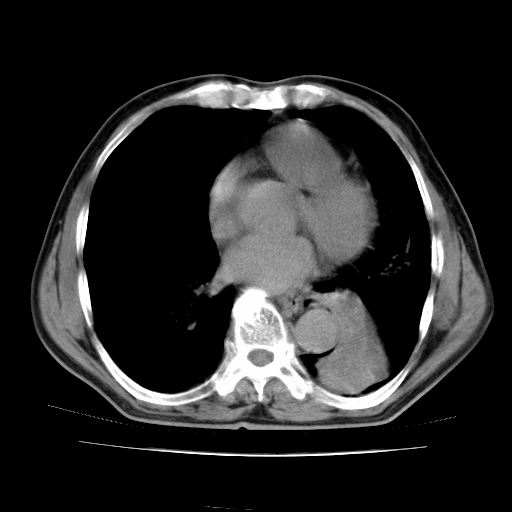

男,71岁,咳嗽,气喘10年,再发并咯血.胸片见气胸

考虑  左肺中心型肺癌伴阻塞性肺炎,肺不张,纵膈淋巴结肿大。慢支炎,肺气肿,左侧气胸肺压缩5%

左侧中央型肺癌伴纵膈淋巴结转移。

左肺中心型肺癌伴阻塞性肺炎,肺不张,纵膈淋巴结肿大

1)考虑左肺中心型肺癌伴阻塞性肺炎、左肺下叶肺不张、左侧肺气肿,纵膈淋巴结转移。2)左侧气胸(肺组织压缩约5%)。

左肺中心型肺癌伴阻塞性肺不张、肺气肿 。

1)考虑左肺中心型肺癌伴阻塞性肺炎、左肺下叶肺不张、左侧肺气肿,纵膈淋巴结转移。2)左侧气胸。